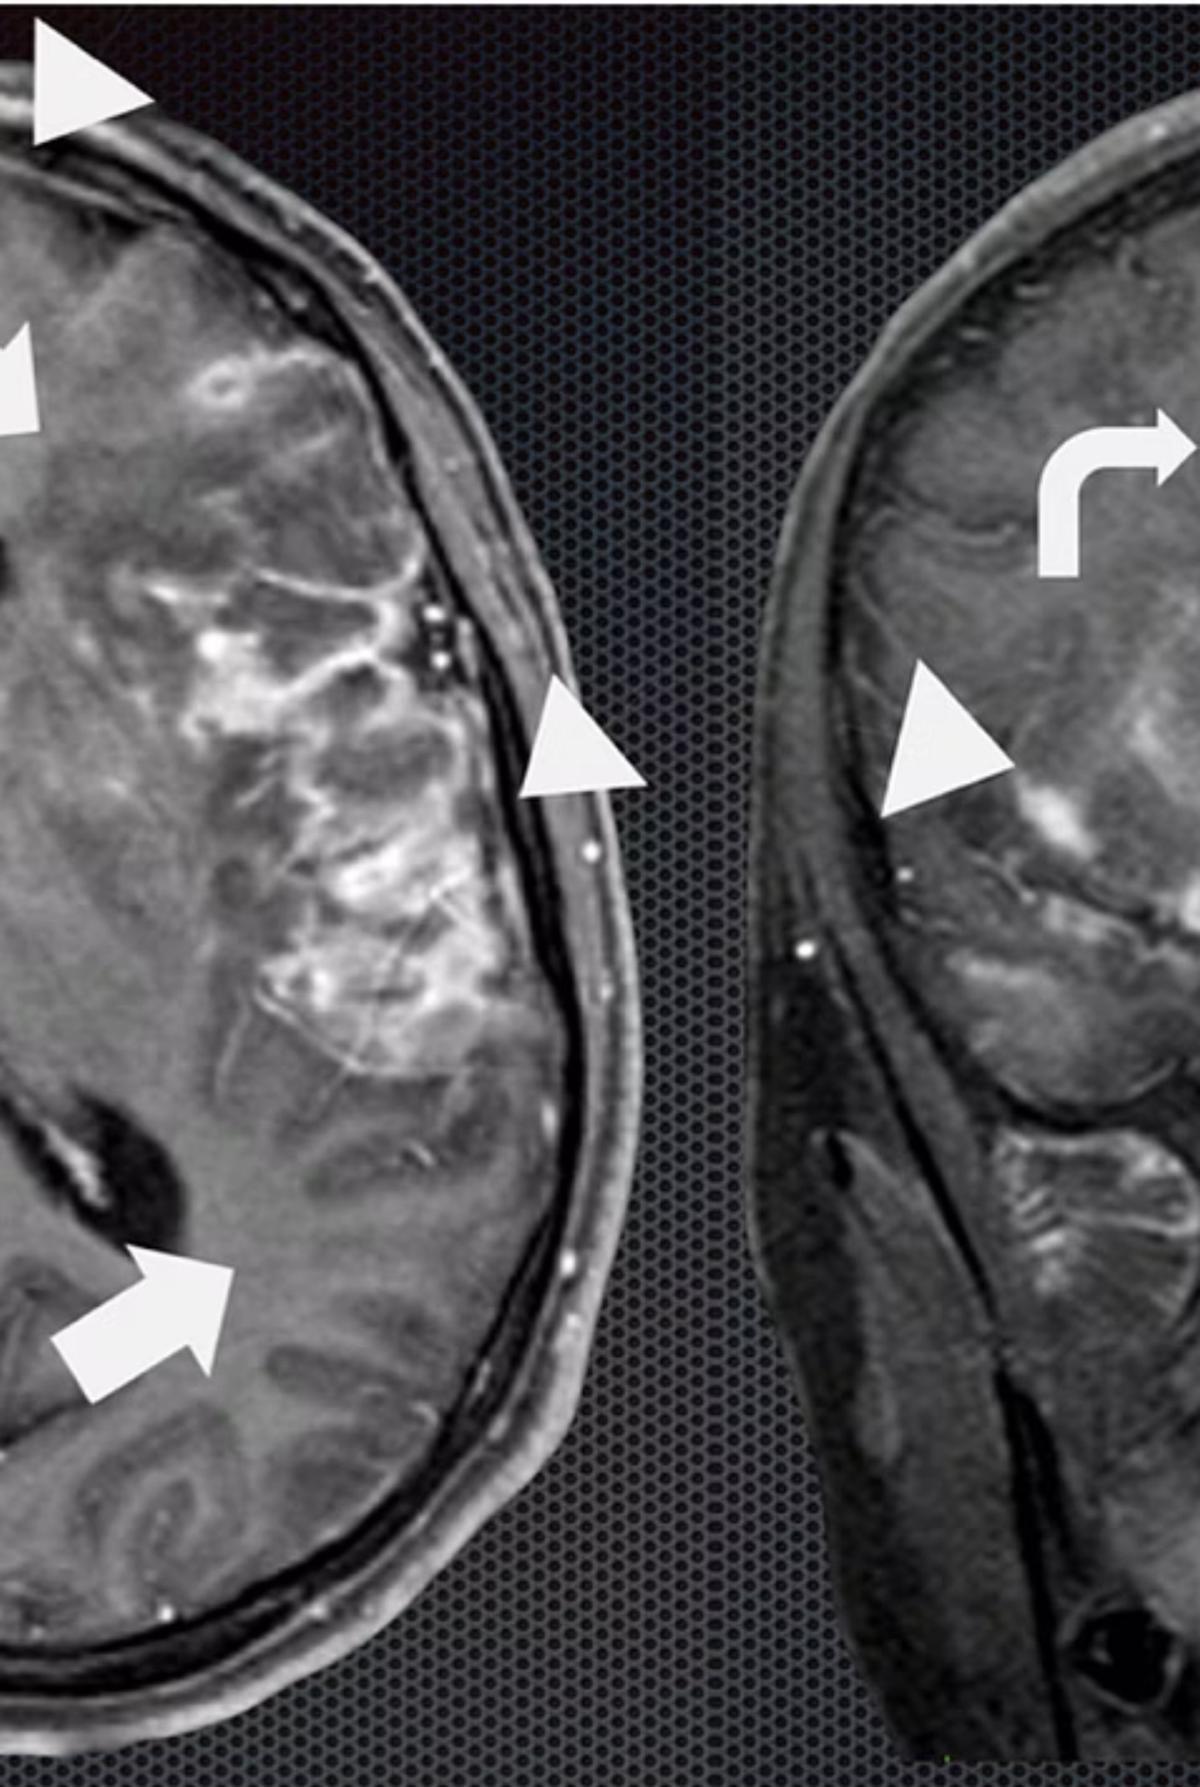

4. Tuberculous Meningitis

Most commonly occurs in children <5 years or immunocompromised patients, often within 6 months of primary infection.

- Pathophysiology: Tubercle bacilli seed the meninges during primary infection, replicate, and trigger inflammatory response leading to basilar meningitis.

- CT Findings: Hydrocephalus, cerebral edema, periventricular lucencies, infarctions.

- CNS Tuberculomas: Occur in 5% of CNS TB cases.